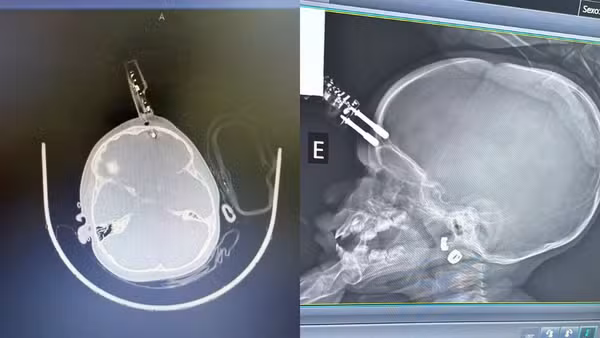

Uma menina de apenas 1 ano foi submetida a uma cirurgia de urgência após sofrer um grave acidente doméstico na cidade de Divinópolis, no Centro-Oeste de Minas Gerais. A criança caiu da cama e teve um carregador de celular cravado na região frontal da cabeça, próximo ao olho. Ela segue internada em observação e, até o momento, não apresenta sinais de sequelas neurológicas, segundo informou o neurocirurgião responsável pelo atendimento, Dr Bruno Castro.

Diante da gravidade do caso, a criança foi levada imediatamente ao centro cirúrgico. No procedimento, a equipe médica realizou a retirada do objeto, limpeza da área, lavagem, fechamento e reconstrução do local atingido.

Segundo o neurocirurgião, o principal risco em casos como esse é a lesão direta ao cérebro, já que o objeto atravessou o osso do crânio e atingiu o tecido cerebral, podendo provocar hemorragias.

“O maior risco do ponto de vista neurológico é o trauma e a lesão cerebral. Esse objeto atravessou o crânio, fincou no cérebro e isso pode ocasionar hemorragia”, explicou.